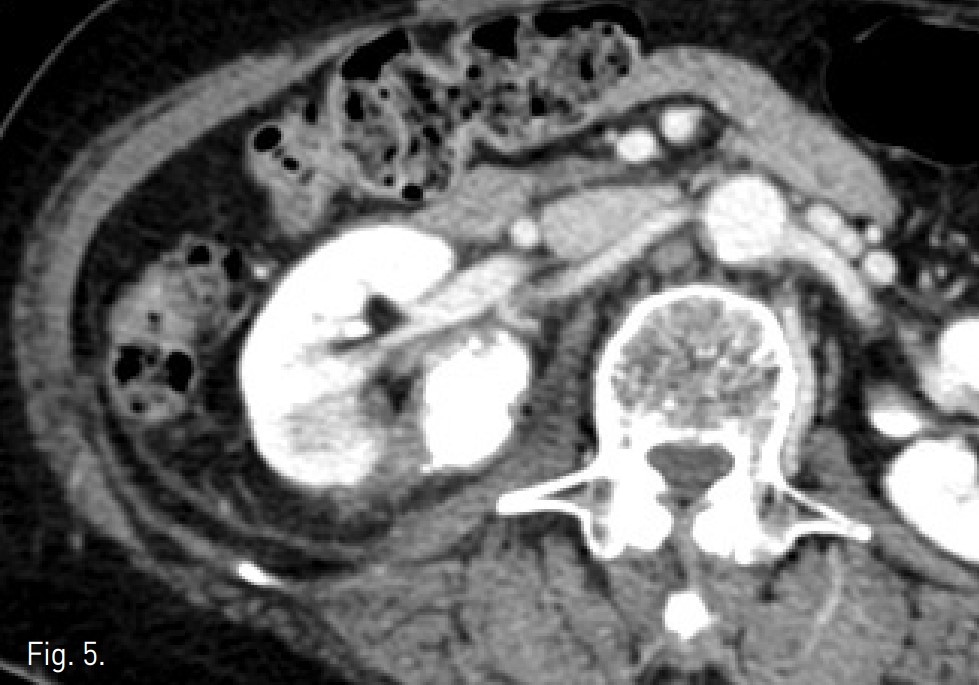

Fig. 5.

Fig 5. Nine months later, follow-up CT demonstrated compact lipiodol up taken nonviable RCC with surrounding RF ablative margin.

CT상 우측 신장 cortex 에 약 3.2cm 크기의 돌출하는 양상의 경계가 좋은 고형 종괴가 있음. 종괴는 신우에 인접해 있었으나 신주위 조직이나 신정맥으로의 침습 소견은 보이지 않았음 (Fig. 1A). 환자가 비수술적 치료를 원하여 고주파열치료를 위해 planning US를 시행하였으나 종양의 에코음영이 신실질과 유사하여 뚜렷이 구별되지 않고 (Fig. 2), 신우에 인접하고 있어 합병증의 위험성이 있고, 고주파 열치료만으로는 충분한 치료가 되지 않을 수 있어서, 동맥 색전술과 고주파열치료의 병합 치료를 하였음. 동맥 색전술과 고주파 열치료를 시행하고 9개월 이후 촬영한 CT에서 우측 신종양은 lipiodol이 compact하게 uptake되었으며 주변에 RF ablation zone이 관찰되고 viable portion이 없는 상태임(Fig. 5).